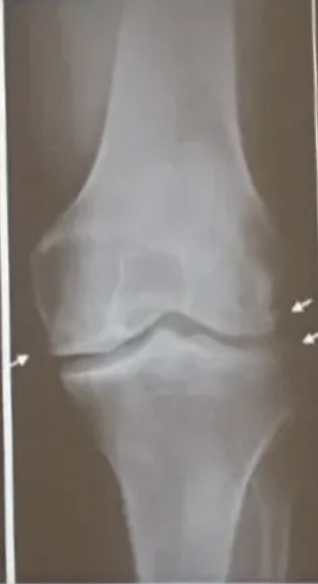

Rx se puede observar

A

• Engrosamiento y esclerosis de la lámina subcondral

• Osteofitos en borde articular

• Distensión de cápsula articular

• Cambios en tejido blando periarticular

Rodillas

• Deformidad → genu varo

• Quistes subcondrales

• Erosiones centrales

• Meseta tibial

osteofitos

Clasificación rx artrosis donde hay ausencia de osteofitos, estrechamiento o quistes

Clasificación rx artrosis donde solo hay osteófitos y dudoso pinzamiento de espacio articular

Grado 1 = dudoso

Clasificación rx artrosis donde hay osteófitos pequeños que estrechan la interlínea moderada, +/- quistes y esclerosis. Claro pinzamiento

Grado 2 = Mínima

Q

Clasificación rx artrosis donde hay osteófitos grandes, estrechamiento de interlinee muy evidente. Colapso de espacio articular, esclerósis severa y deformidad ósea

Grado 4 = Severa